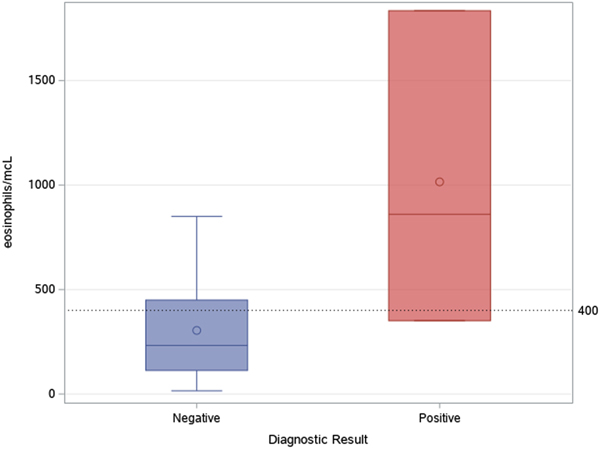

An 85-year-old patient with moderate-severe chronic renal failure, insulin-dependent diabetes mellitus with peripheral polyneuropathy, COPD, prostatic hypertrophy and rheumatic polymyalgia with probable small-vessel vasculitis was admitted to the State Hospital in San Marino on the 8 March 2017 for fever, asthenia and hyporexia. Blood tests showed hypochromic microcytic anaemia (haemoglobin 9.2 g/dl), mild eosinophilia (558 eosinophils/μl), hyperglycaemia (265 mg/dl), increased erythrocyte sedimentation rate (99 mm/h, normal values <13) and CRP (8.43 mg/dl, normal values <1). Two sets of blood culture were negative. During the first days of hospitalisation, he was kept on his usual therapy, which included prednisone 12.5 mg/day. On the 13th March a contrast-enhanced CT scan was done, showing diffuse bowel and gastric wall thickening, thickening of the bronchial walls and pulmonary interstitial oedema. A colonoscopy demonstrated a flat lesion in the right colon, intestinal inflammation, ulcers and petechial spots (Fig. 3). The histological examination revealed lymphoplasmacellular and eosinophilic infiltration, epithelioid granuloma and multiple S. stercoralis larvae (Fig. 2b). Also, intranuclear inclusion bodies compatible with cytomegalovirus (CMV) infection were found; this infection was confirmed by PCR on blood, that showed 1888 UI/l viraemia. On the 16 March treatment with ivermectin 200 μg/kg/day and piperacillin/tazobactam 2.25 g three times a day (dosage adjustment for renal failure) was started. The dose of prednisone was gradually reduced. In the meantime, also stool examination, PCR and IFAT resulted in positive for S. stercoralis. Hence, on the 20 March, albendazole 400 mg twice a day was added. The general condition of the patient gradually improved, and CMV viraemia reduced spontaneously along with clinical recovery. Antihelminthic therapy was stopped 2 weeks after negativisation of stool microscopy, that was achieved after 21 days of treatment. The patient was discharged on the 7th April, in fair clinical condition. On the 30 May, he underwent a colonoscopy that showed almost complete resolution of the inflammation. The biopsy of the flat lesion (observed also in the previous examination) demonstrated a villous adenoma.

Fig. 3. Erythematous and oedematous mucosa of the transverse colon, with aphtoid ulcers and petechiae.